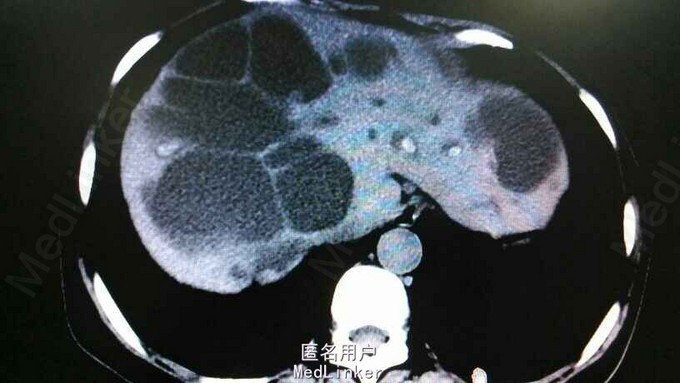

查体:右上腹轻压痛,无反跳痛,余无特殊。辅助检查,肝功,血象正常。腹部CT示肝内多发结石伴胆管囊状扩张。胆总管结石。见图

诊断:肝胆多发结石。治疗:予覆盖敏感菌,利胆等治疗。外科会诊:无法手术,内科治疗为主。

患者肝功正常,目前右腹疼痛考虑感染或是结石所致炎症可能,抗感染等治疗后症状好转出院。